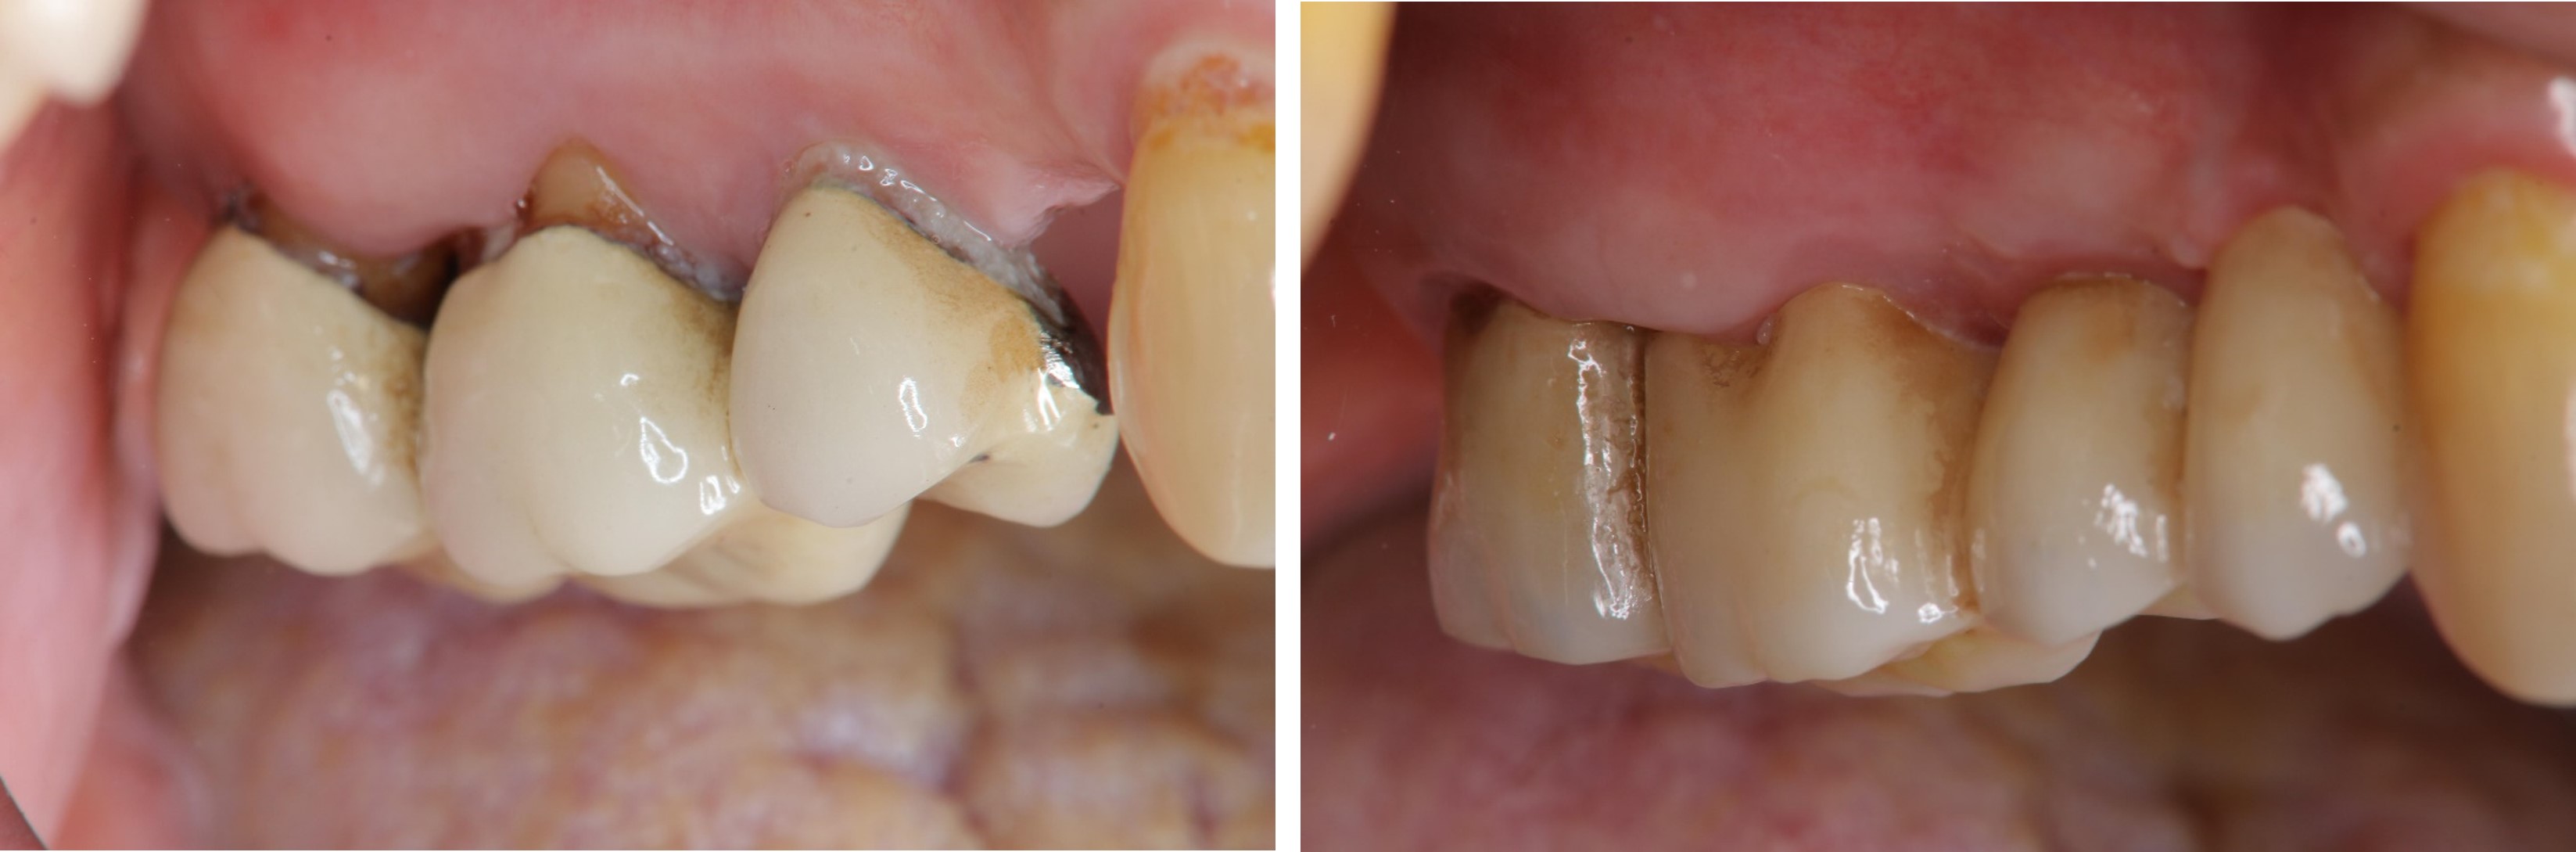

治療後,咬合良好

治療後,密合度良好

術前、術後比較